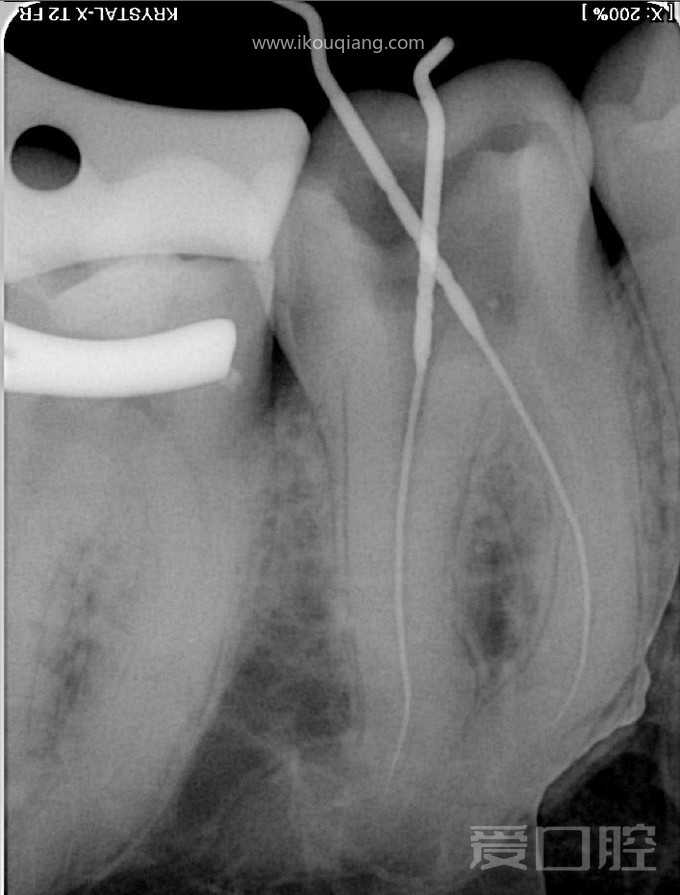

看个根充 —— 下颌第一磨牙